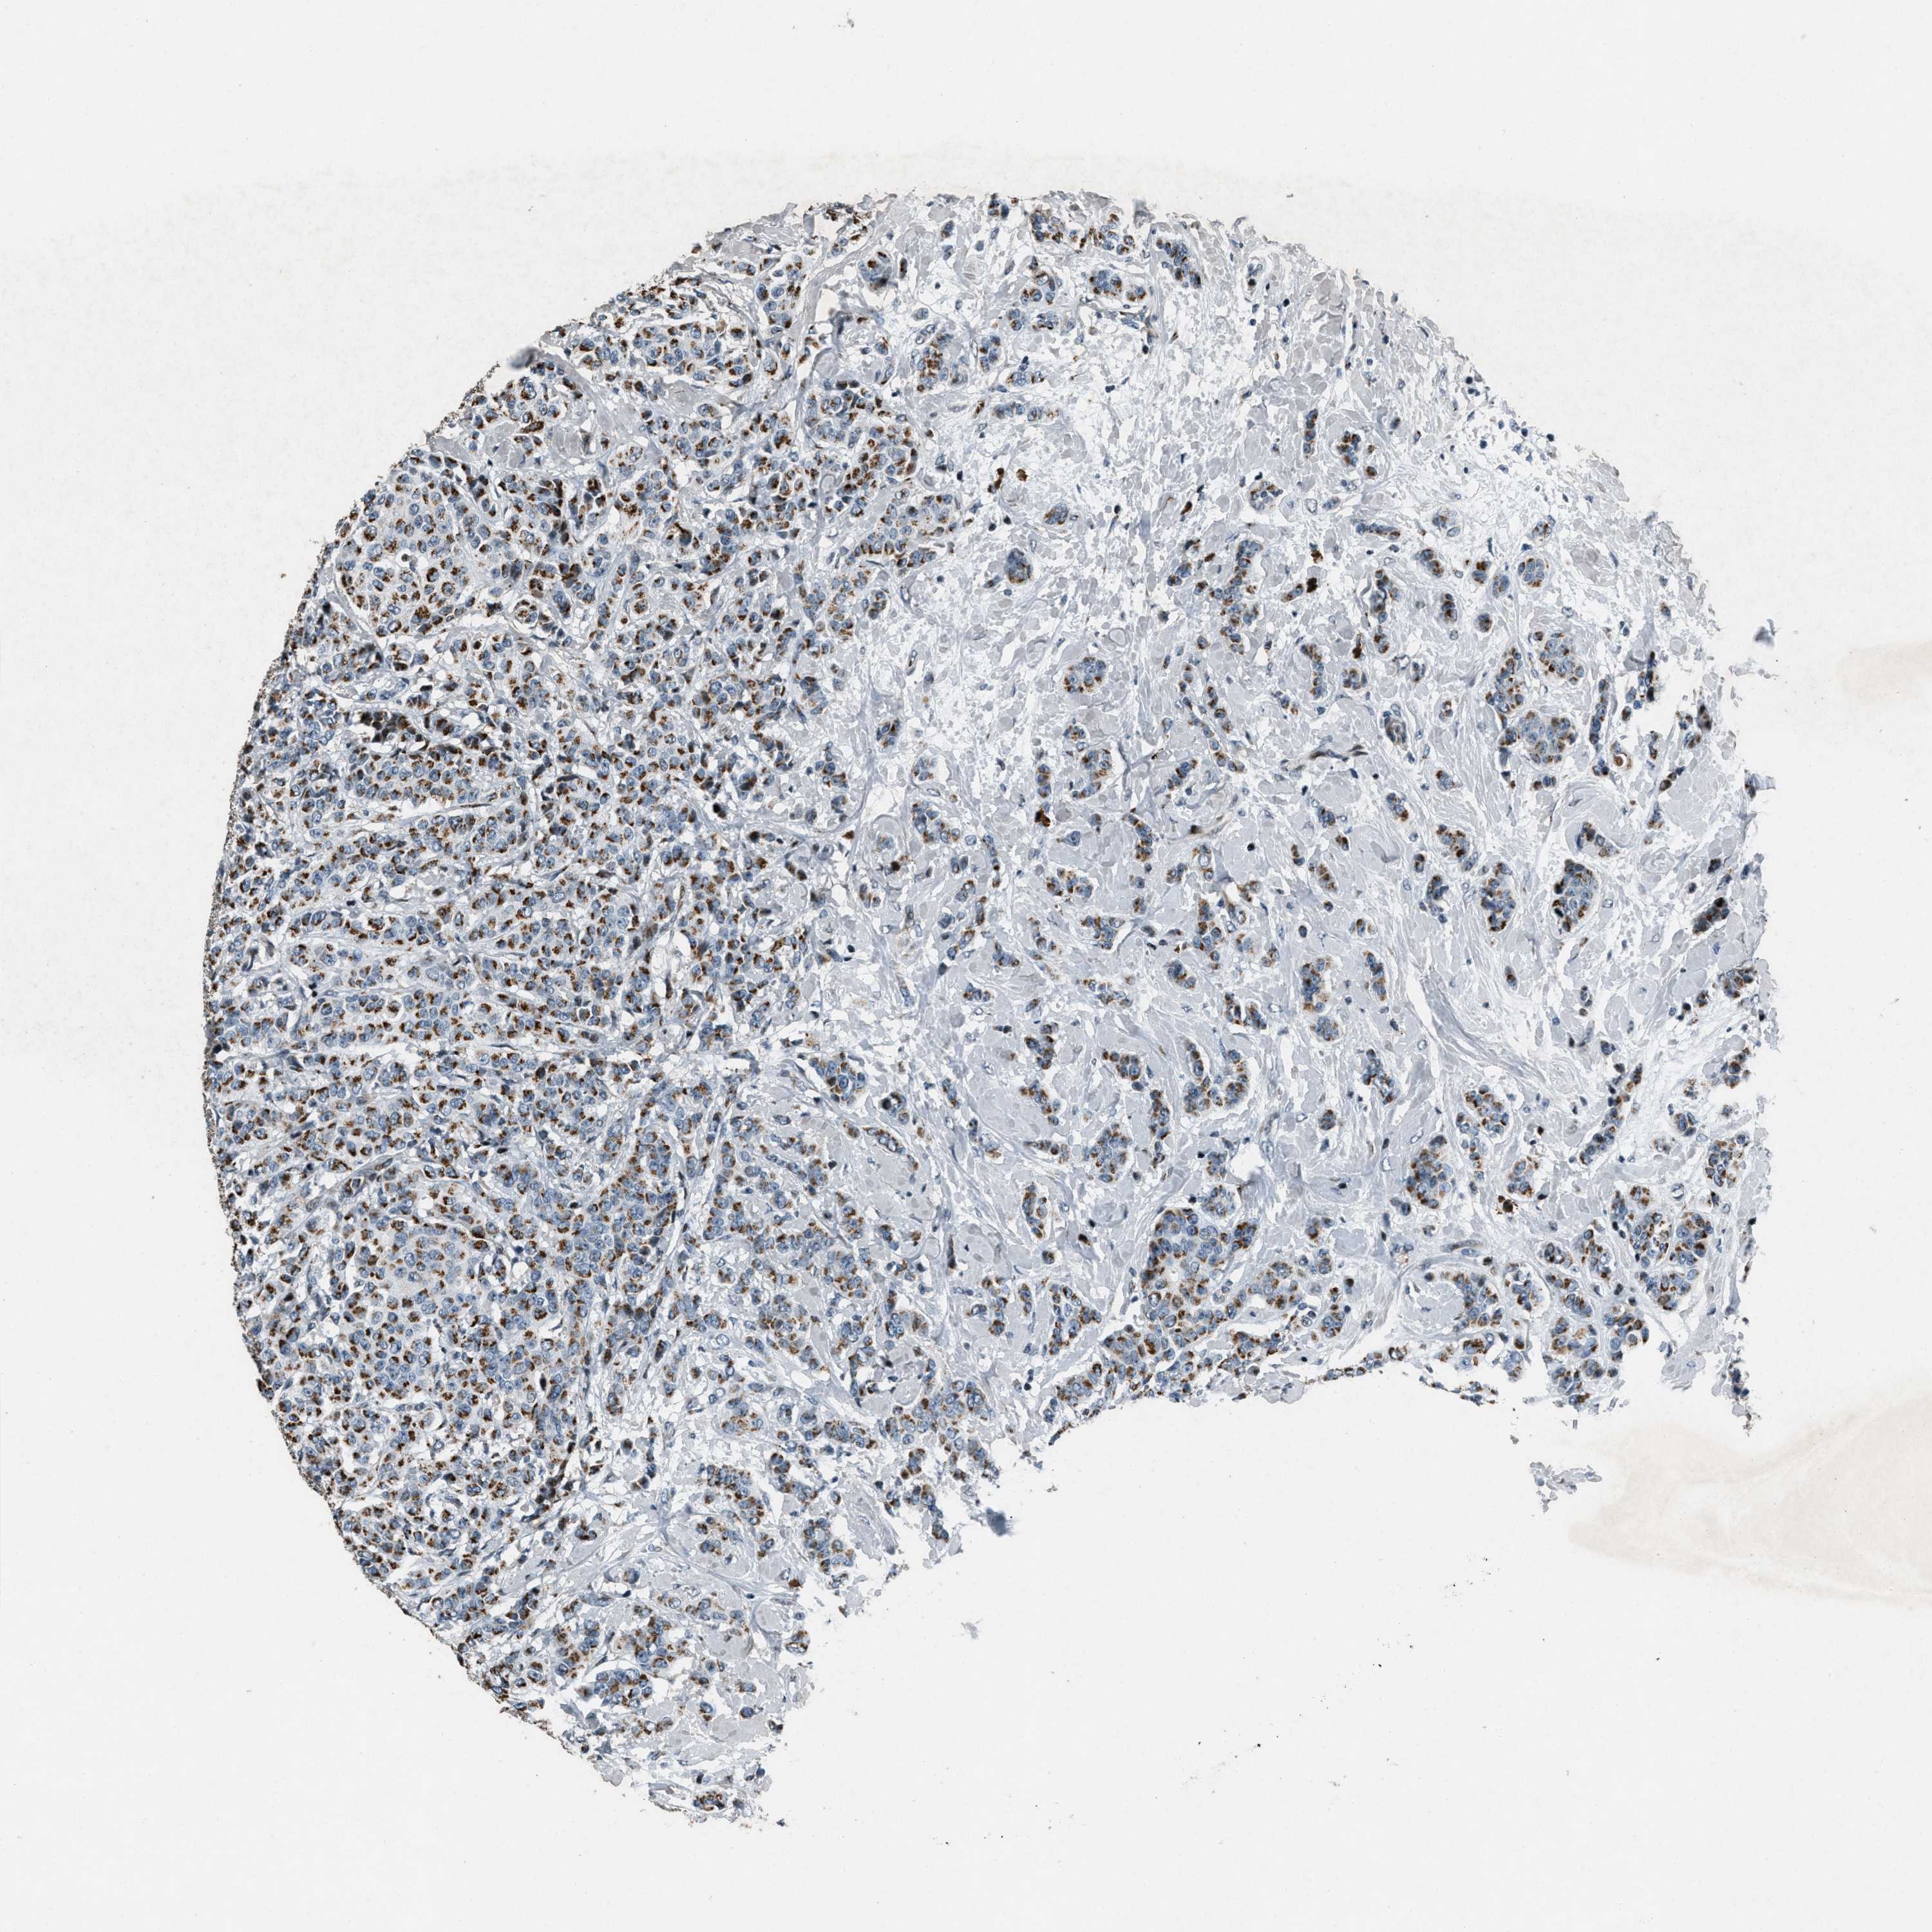

CANCER BREAST CANCER Show tissue menu

BRCA TCGA BRCA VALIDATION PROTEIN EXPRESSION